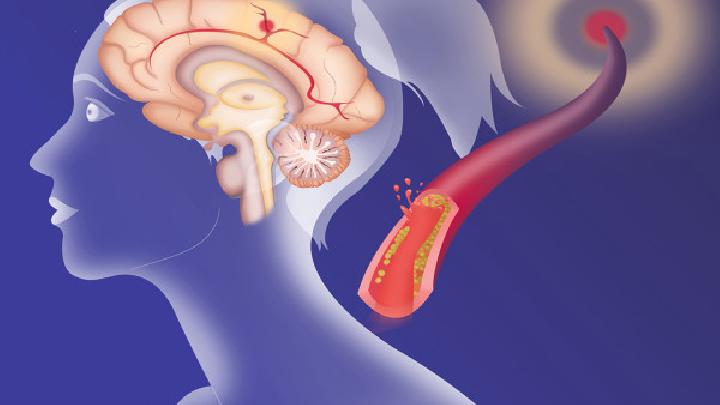

抓住脑卒中康复的“黄金时间窗”

脑卒中康复患者的功能恢复主要发生在病后6个月内,尤其是头3个月内,实践证明,脑卒中在发病的半年之内,是肢体功能恢复的时期,切不可忽视,要重视合理的康复治疗,尽早进行。 脑卒中的康复治疗要根据病情越早越好,一般来说,缺血性脑卒中患者,只要神智清楚,生命体征平稳,病情不再发展,48...